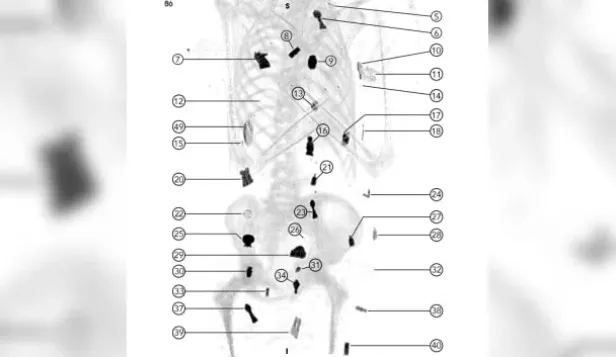

Un escáner realizado por científicos de Egipto reveló que la momia conocida como el “niño de oro”, con una antigüedad de unos 2.300 años y con un nivel socioeconómico alto, contaba con un total de 49 amuletos de 21 tipos diferentes y que fueron colocados en su cuerpo o en su interior.

Según el artículo publicado por la revista ‘Frontiers in Medicine’, el sarcófago estaba ataviado con sandalias y guirnaldas de helechos, que contaban significado ritual. Entre los amuletos, se encontraron algunos como un escarabajo de oro con forma de corazón, ubicado en el interior de la cavidad torácica, y una lengua de oro dentro de la boca. Los investigadores señalaron que las momias “representan una oportunidad para conocer mejor la salud, las creencias y las habilidades de los humanos de la Antigüedad”.

Otro de los amuletos hallados era uno de dos dedos junto al pene incircunciso. El sexo biológico del individuo pudo determinarse mediante una tomografía computarizada, y por la presencia de genitales masculinos. Por otro lado, factores como la fusión epifisaria y la erupción dentaria indicaron una edad aproximada de unos 14/15 años en el momento de la muerte.